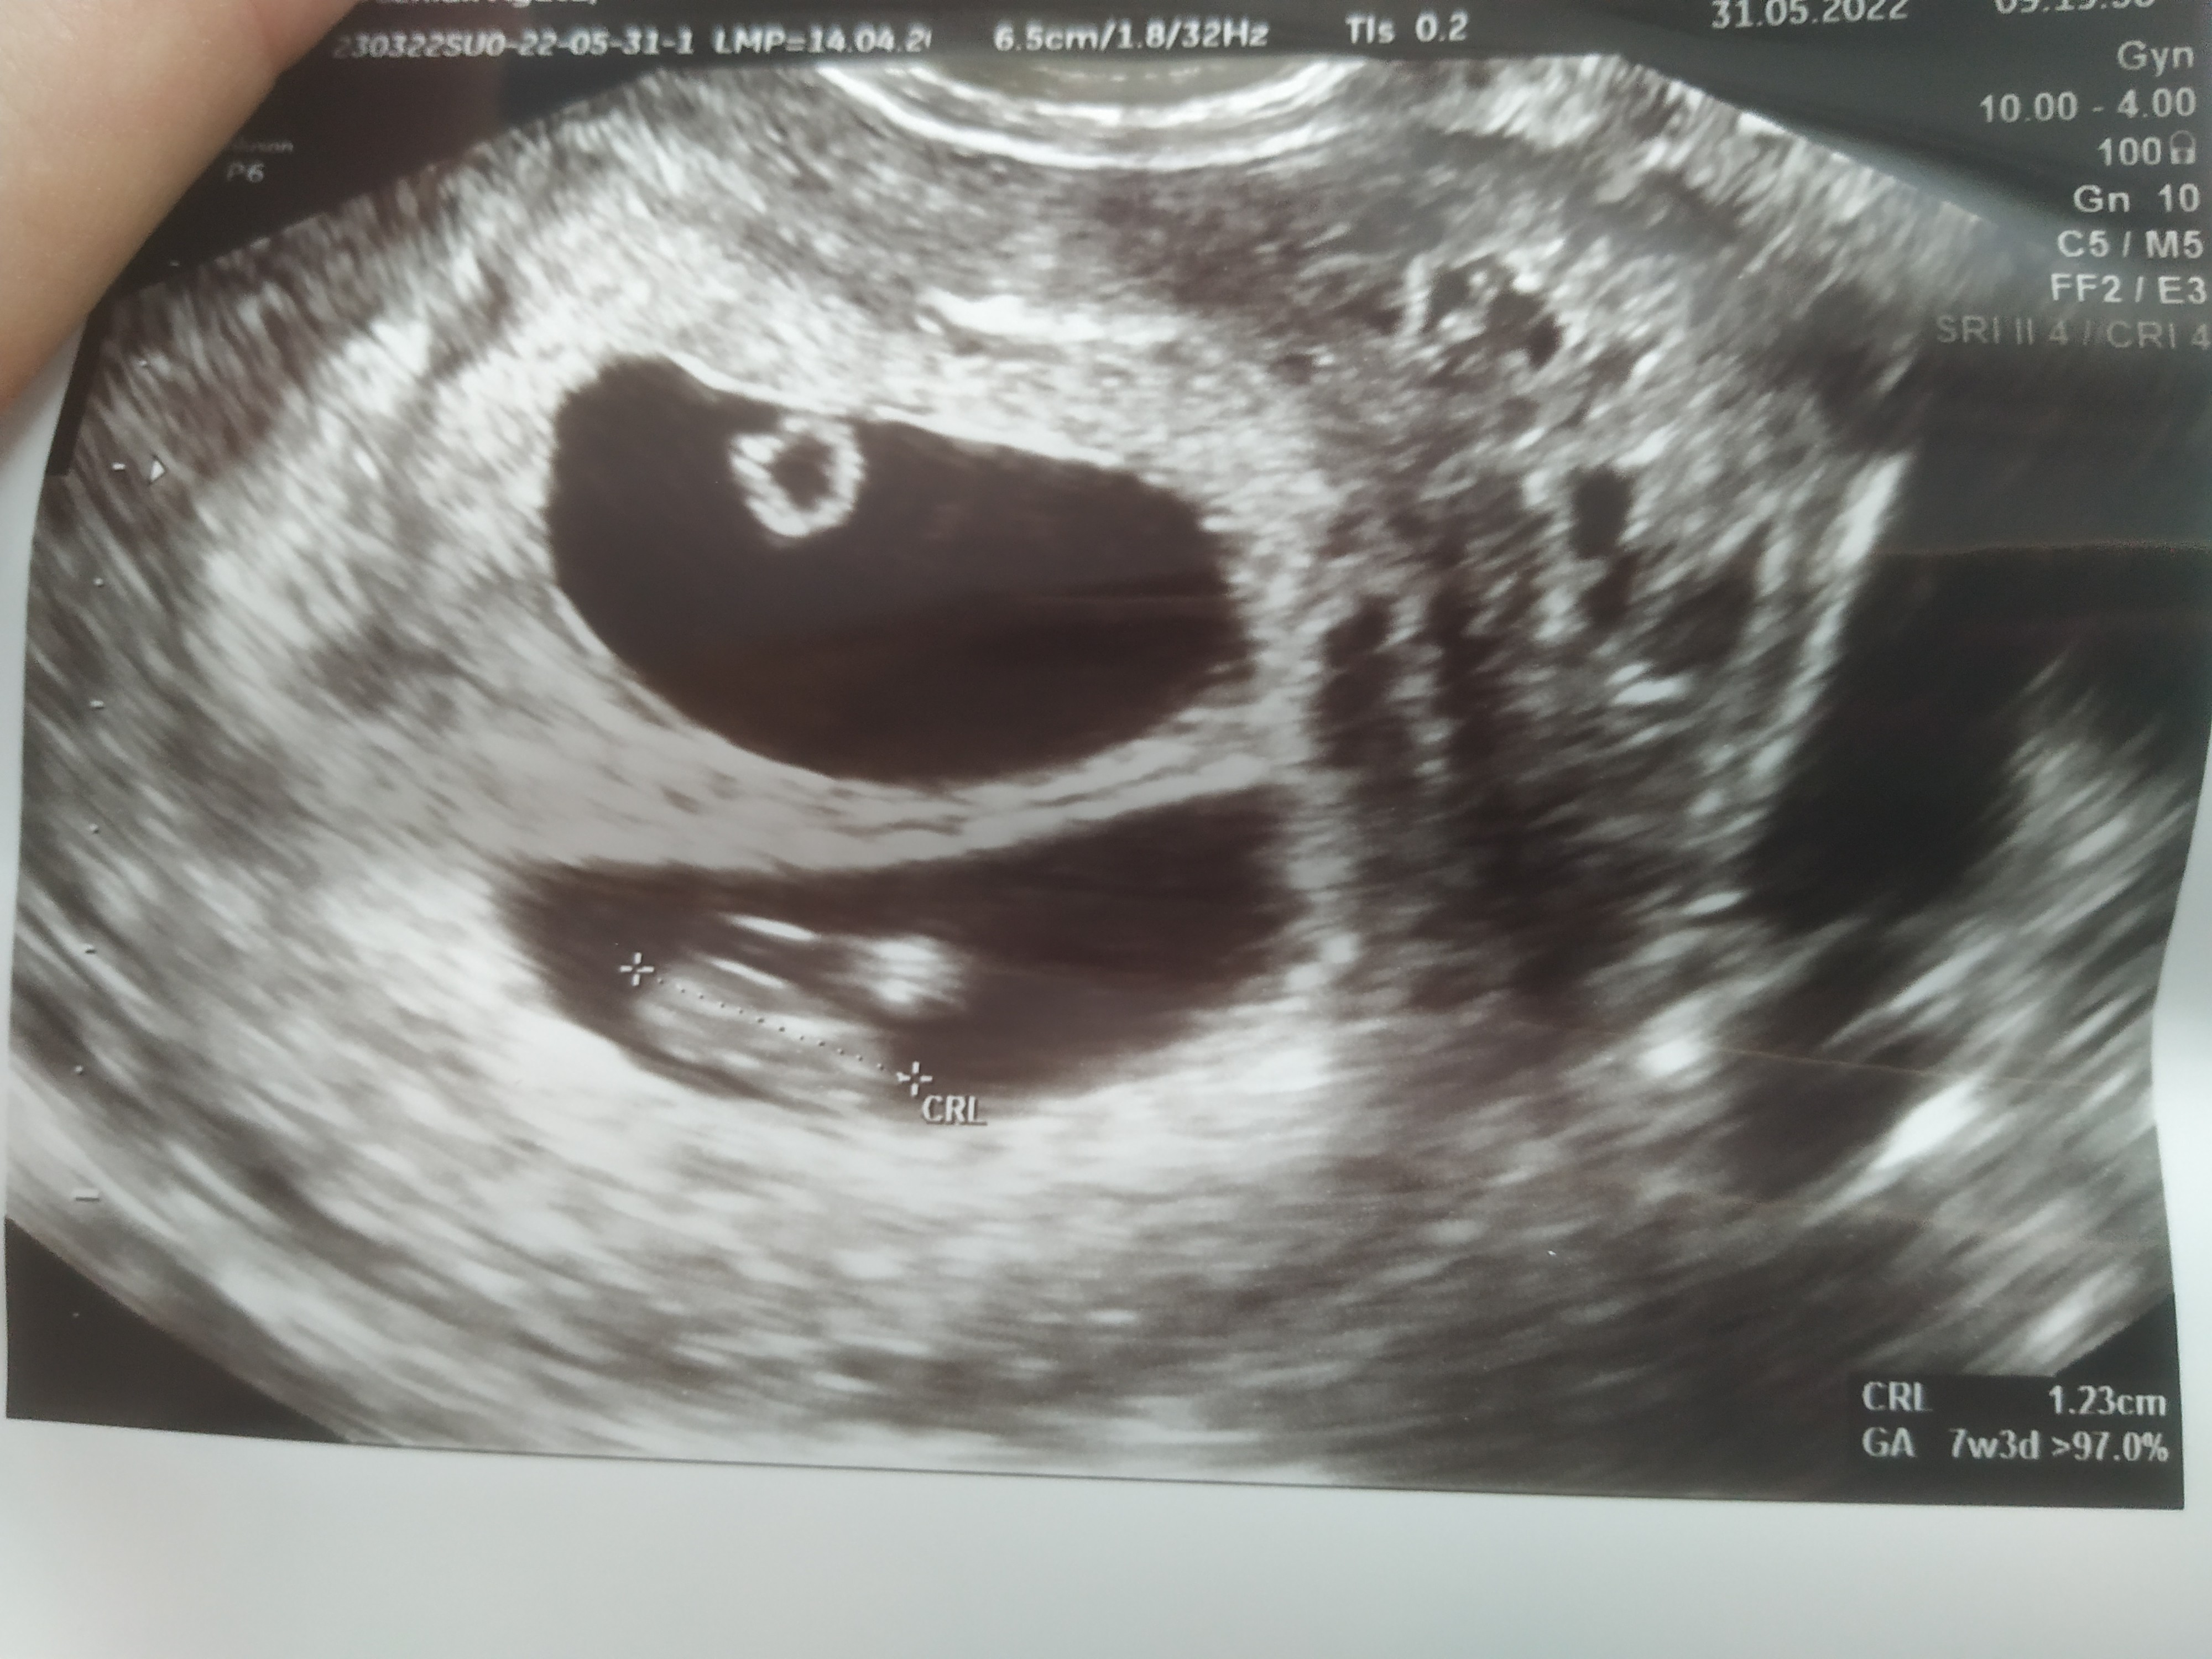

Witam, w piątek byłam u ginekologa który zobaczył 3 pęcherzyki ciążowe.

Wczoraj kolejna wizyta i tylko jeden, w sumie lekarz coś mówił że jest drugi ale mały.

I tu moje pytanie czy ten mały to może być krwiak? Czy jest szansa, że to ciąża bliźniacza? Zobacz załącznik 1421172Zobacz załącznik 1421173